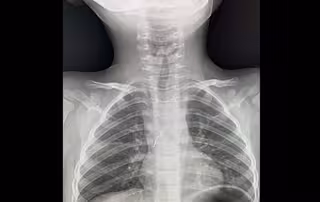

Чергові лікарі зробили рентген і побачили стороннє тіло у дихальних шляхах. Діставали його з допомогою бронхоскопії, тобто без жодного розрізу.

«Гострими, направленими в різні сторони вусиками лампочка »дивилася« на мене. Вуса під час дихання травмували слизову оболонку в ділянці біфуркації трахеї, там уже утворилися дрібні крововиливи. Я захопив вусики щипцями і завів їх у тубус бронхоскопа, щоб під час видалення не травмувати ними бронхи і трахею. Разом з тубусом дістав лампочку з бронха дитини», — пояснив торакальний хірург Олександр Колодій.